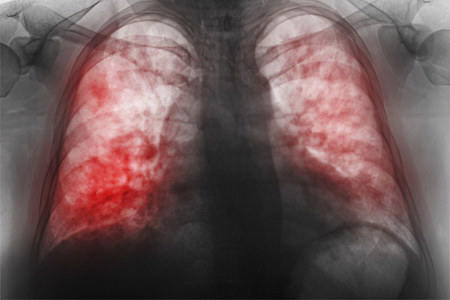

7 самых опасных мифов о пневмонии, которые стоит знать

Миф 1. Пневмония – неопасная болезнь

Не все знают, что в начале XX века 85% людей, заболевших пневмонией, умирали. С открытием антибиотиков ситуация улучшилась, но считать эту болезнь безопасной — серьезная ошибка.

Главный пульмонолог России, академик РАН А. Г. Чучалин, относит воспаление легких к числу самых опасных инфекций на планете. По данным Всемирной организации здравоохранения, пневмония занимает четвертое место среди причин смертности. Даже при легкой форме заболевания 5% пациентов могут погибнуть, а при осложненной пневмонии этот показатель возрастает до 25-50%! Уровень смертности продолжает расти из-за устойчивости бактерий к антибиотикам, и в настоящее время он увеличился еще на 9%.

Для установления диагноза «пневмония» необходимо провести обследование, в первую очередь рентгенографию легких.